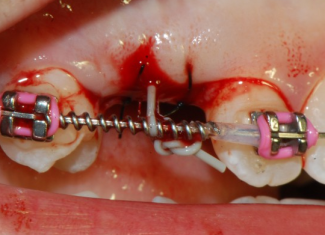

Se un dente definitivo non erompe e vi sono le indicazioni per il suo recupero, effettuato un lembo gengivale e messo a nudo il dente, vi si applica un bottone ortodontico o un apposito pernino e tramite un filo metallico lo si posiziona nella sua sede.